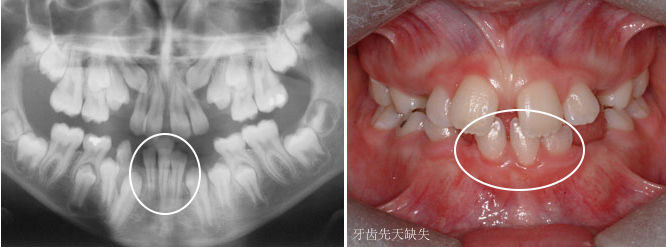

如果牙齿比平均该长牙的年龄,晚了12个月还没有长牙的话,叫做牙齿迟萌。造成牙齿迟萌的原因有很多,比如,多生牙、牙瘤、囊肿会导致牙齿迟萌。

一些先天性疾病(如颅锁骨发育不全综合征)也会导致牙齿迟萌,但较为罕见。

如果你家孩子比平均该长牙的年龄,晚了12个月还不长牙,你需要及时带孩子看牙医了。牙医一般会拍牙片来看看牙床内是否有未萌出的牙齿。